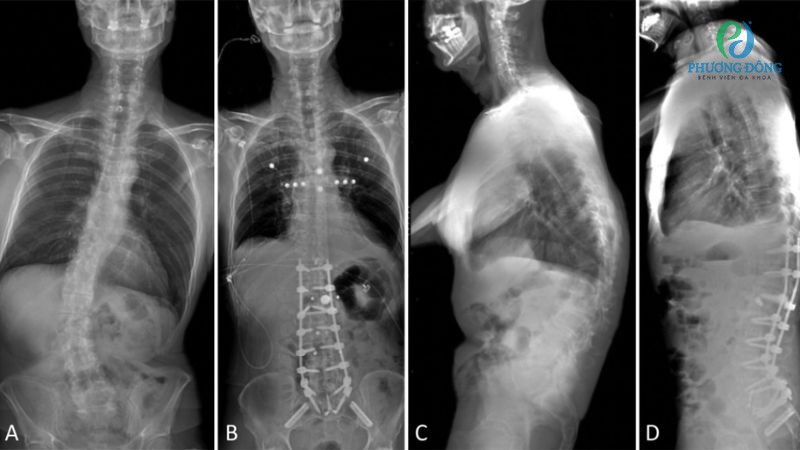

- Phẫu thuật: Những trường hợp bệnh tiến triển nặng, không đáp ứng thuốc hoặc không cải thiện sau quá trình vật lý trị liệu sẽ xem xét áp dụng can thiệp ngoại khoa. Tuy nhiên hậu phẫu, bệnh nhân cần được theo dõi và chăm sóc sức khỏe kỹ lưỡng.